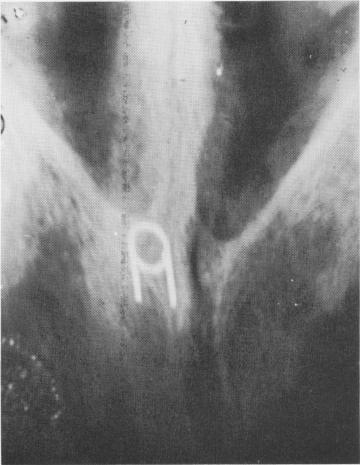

Fig. 4-67. Under low power, a longitudinal section from a bone block around a metallic implant shows dense bone separated from the implant site (X) by a fibrous tissue membrane. (Courtesy K. R. Blakey, Howard University.)